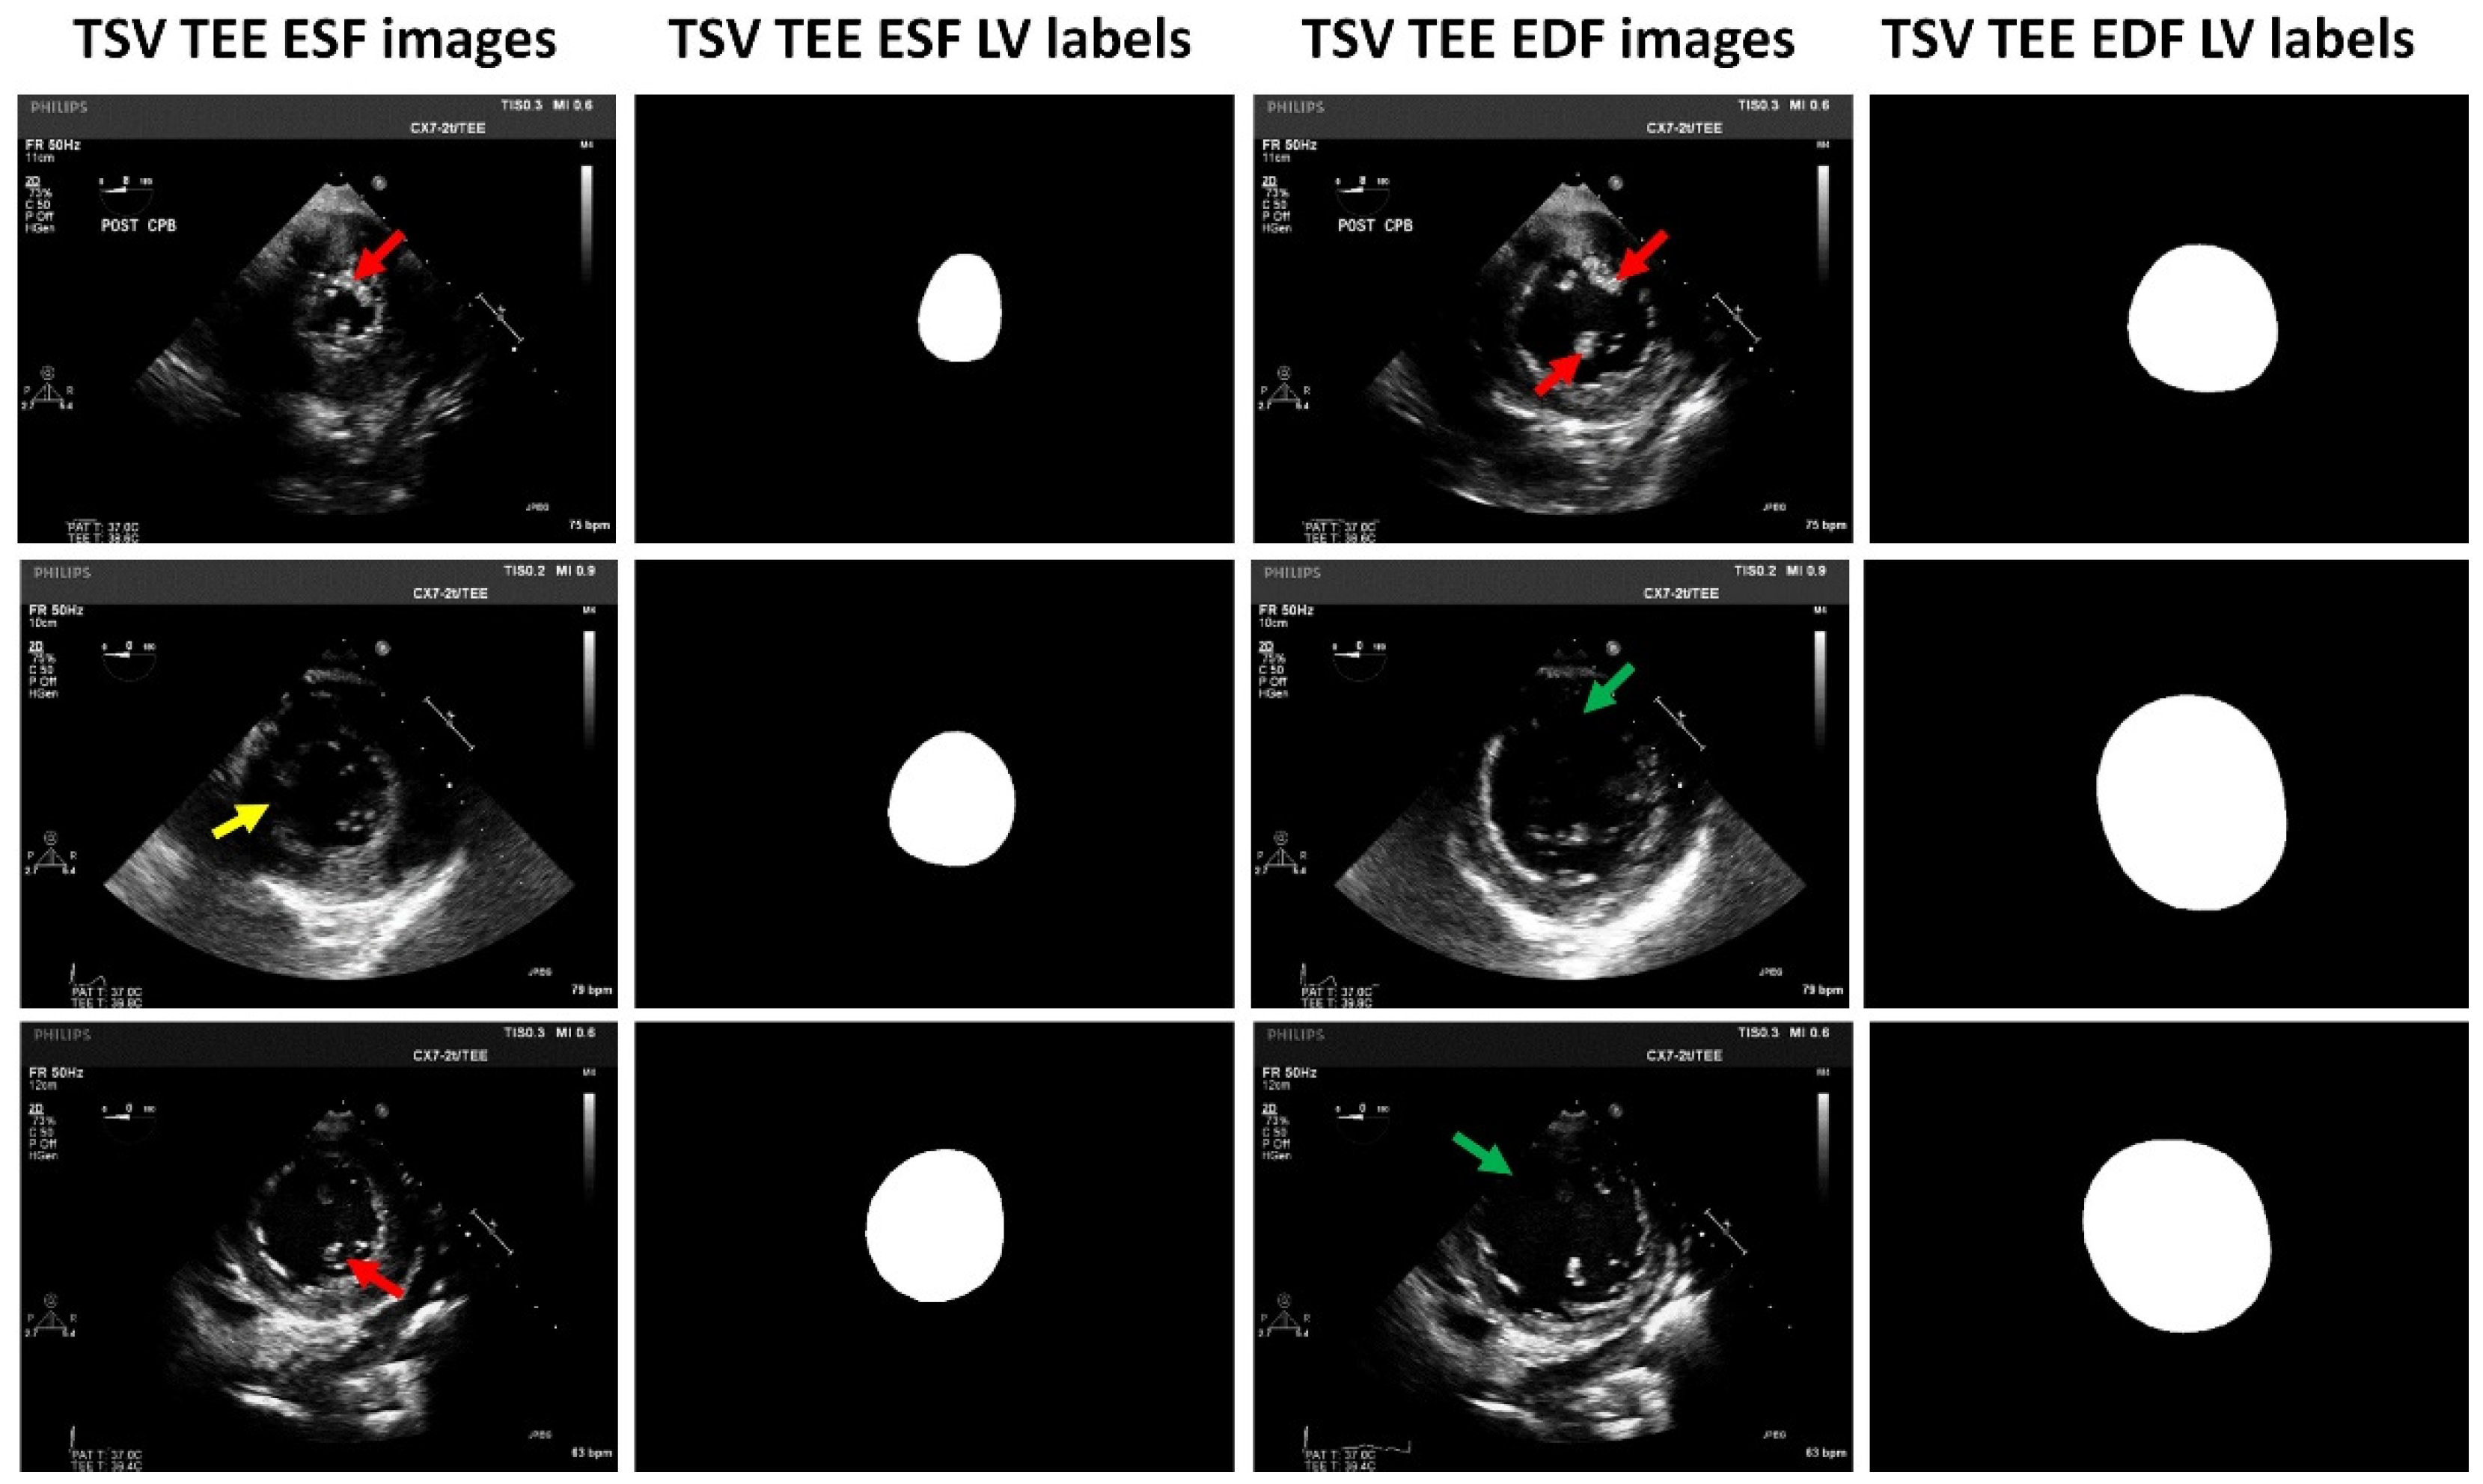

2. Materials and Methods

2.1. Patients Enrollment and Dataset Formulation

2.2. Data Preprocessing and Augmentation